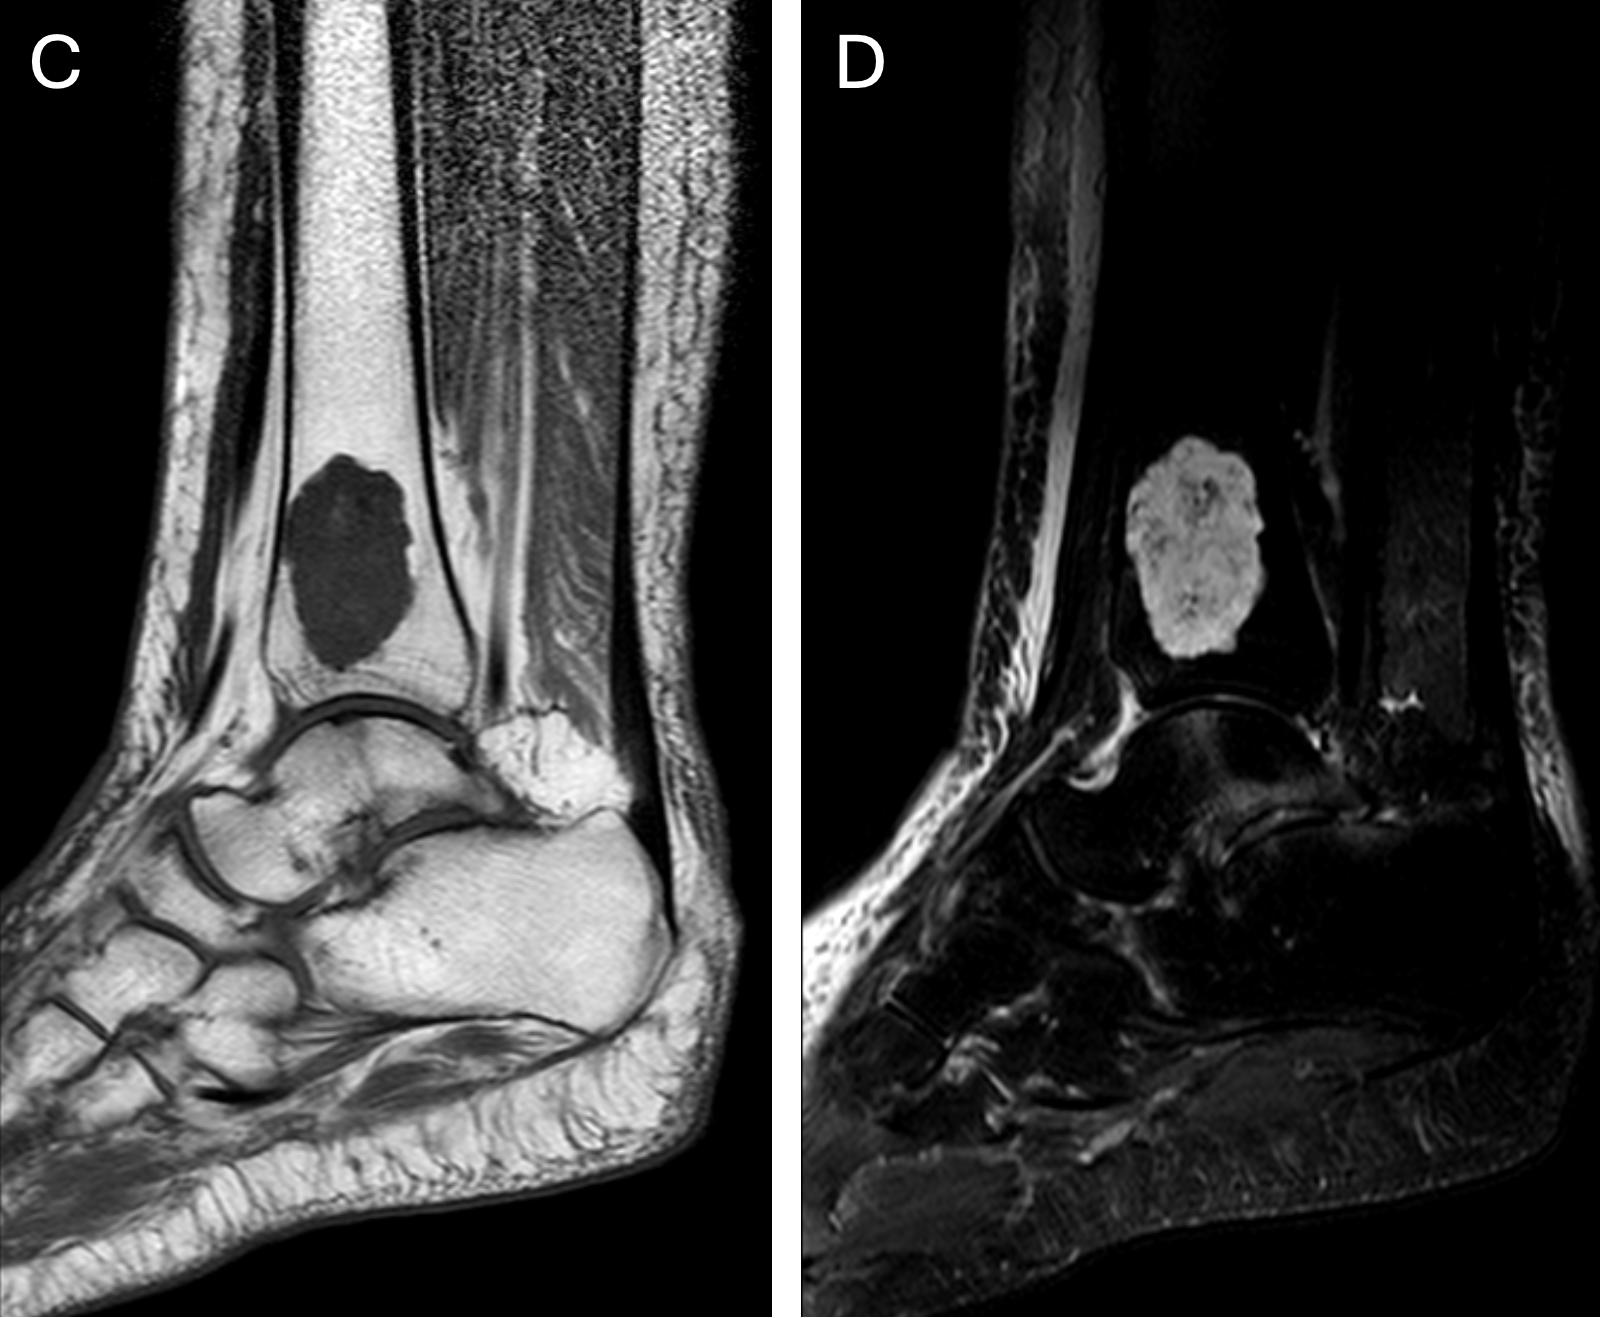

Bei der Pathologie auf einem der vorliegenden MRTs handelt es sich um ein Echondrom, bei der anderen Pathologie um einen Knocheninfarkt. Abbildung 1 – Knie-MRT: A) koronare T1w B) koronare T2w mit Fettunterdrückung Abbildung 2 – Sprunggelenks-MRT: C) sagittale T1w D) sagittale T2w mit Fettunterdrückung Bei welcher Untersuchung würden Sie eher einen Knocheninfarkt vermuten und bei welcher ein Enchondrom? Begründen Sie Ihre Entscheidung.